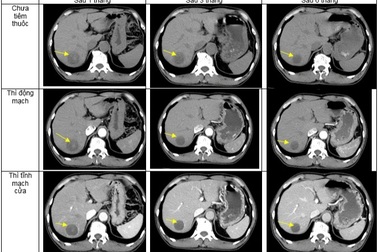

Phản ứng da nghiêm trọng khi dùng thuốc trị ung thư atezolizumabAtezolizumab là loại thuốc kháng thể đơn dòng được sử dụng để điều trị ung thư biểu mô đường niệu, ung thư phổi không phải tế bào nhỏ, ung thư vú thể 3 âm tính, ung thư phổi tế bào nhỏ và ung thư biểu mô tế bào gan.